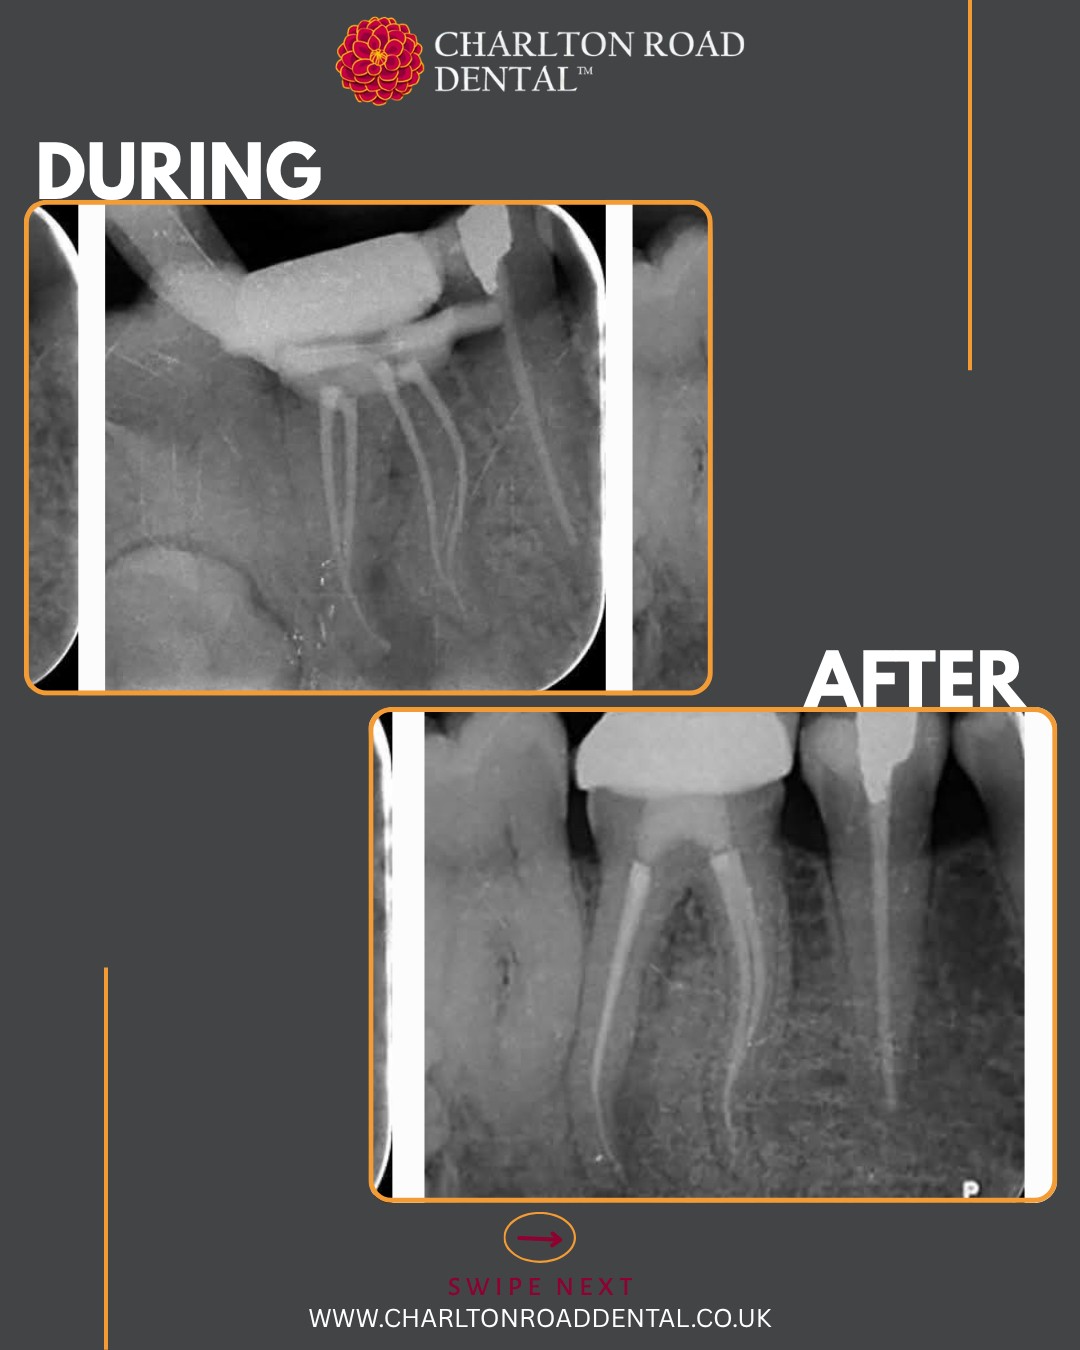

I prepared the DB and palatal roots first, allowing the MB root to soak in disinfection solution in the meantime. I instrumented the MB root system up to size 20/06, and up to 25/06 in the palatal and DB roots. Irrigation was performed using full-strength sodium hypochlorite and Endo solution, delivered with Irriflex tips. I used a yellow EndoActivator for agitation and micro-suction to dry the canals.

Total Fill sealer was placed and carried to working length using a size 25/029 gutta-percha point. I customised a size 20/029 GP point for the MB root, a 25/029 GP point for the DB root using a taper plate, and used a master fit GP point for the palatal root. The tooth was then sealed with LuxaCore.

Each tooth is as unique as a fingerprint, so a flexible, hybrid approach was taken to cleaning and preparing the canals prior to obturation.